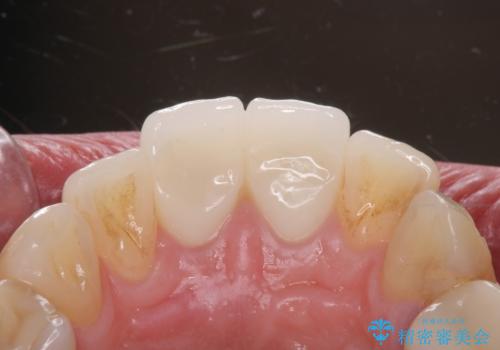

先端に透明感のあるかぶせ物を装着することで審美的な問題を解決しつつ、少しガタついていた歯並びも改善することができました。